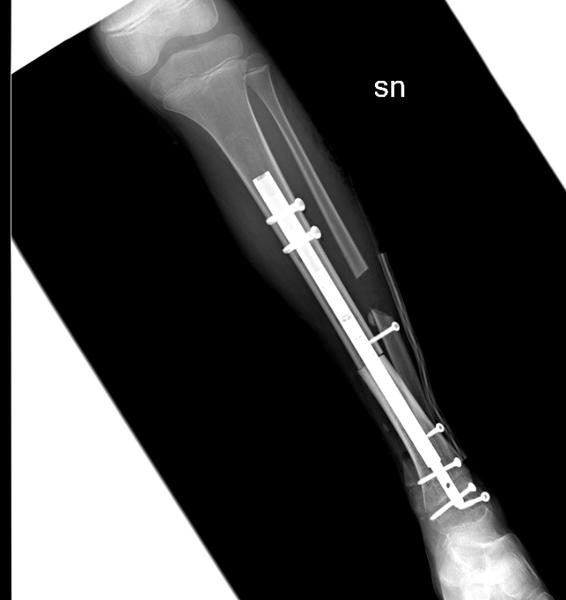

La procedura chirurgica è stata effettuata da un’équipe di ortopedici coordinata dal dottor Raimondo Piana (Chirurgia Oncologica e Ricostruttiva dell'ospedale CTO di Torino) insieme al dottor Marco Manfrini ed alla dottoressa Laura Campanacci della Clinica di Ortopedia Oncologica del Rizzoli diretta dal professor Davide Donati. La bimba, dopo la diagnosi, è stata sottoposta a chemioterapia presso il reparto di Oncoematologia pediatrica dell’ospedale Regina Margherita (diretto dalla professoressa Franca Fagioli) e nei giorni scorsi è stata sottoposta all’intervento di asportazione del tumore e salvataggio della caviglia con ricostruzione con osso omoplastico da donatore e sintesi con un chiodo allungabile, in modo da permettere la regolare crescita dell’arto senza necessità di ulteriori interventi.

La tecnica eseguita rappresenta una assoluta novità in quanto il chiodo inserito per stabilizzare l’impianto permetterà nei prossimi anni anche la regolare crescita dell’arto permettendo l’allungamento al termine della maturazione scheletrica. La chirurgia è stata pianificata nei minimi dettagli dalle due équipes di medici ed ingegneri nelle settimane precedenti. Nonostante la pandemia da Covid-19 le cure legate a questo tipo di patologie si sono svolte regolarmente e senza ritardi. La bimba ora sta bene ed è stata appena dimessa.Negli ultimi 30 anni si è vissuta la straordinaria evoluzione di nuove tecniche chirurgiche specifiche per lo scheletro infantile, riducendo drasticamente il numero di amputazioni e riuscendo ad applicare nella maggior parte dei casi un approccio conservativo - ricostruttivo, volto a migliorare il recupero funzionale e ad assicurare una migliore qualità di vita ai pazienti e alle famiglie.